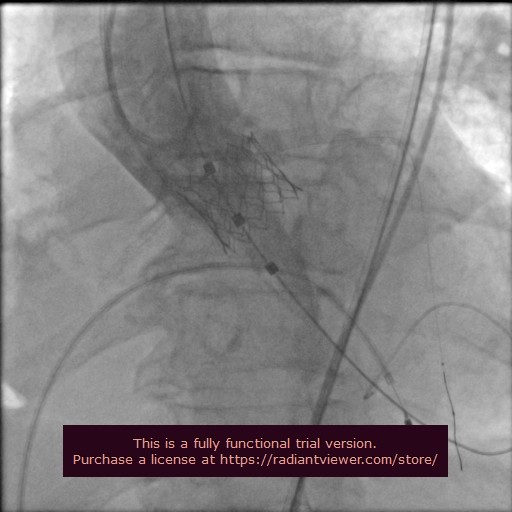

İleri evre aort kapak darlığı nedeniyle yaşamını doktor takibinde sürdüren 88 yaşındaki Ali Güvensoy'un kalp yetmezliği şikayeti, son iki ayda birkaç kez hastanede yatış gerektirecek kadar ciddi boyuta ulaştı. Bu durum Ali Güvensoy'un aort kapakçığına müdahaleyi zorunlu hale getirdi. Dr. Suat Günsel Girne Üniversitesi Hastanesi hekimlerince değerlendirilen hastanın açık kalp cerrahisi risk puanının yüksekliği ve genel durumunun açık kalp ameliyatını kaldıramayacak düzeyde olması nedeniyle, operasyonun ameliyatsız TAVİ yöntemi ile yapılmasına karar verildi.

Geçtiğimiz günlerde Prof. Dr. İlker Gül başkanlığında Kardiyoloji, Kalp Damar Cerrahisi ve Anesteziyoloji ve Reanimasyon Anabilim Dalı ile anjiyografi laboratuvarı ekipleri tarafından gerçekleştirilen işlemle Ali Güvensoy kalp sağlığına tekrar kavuştu.

İşlem öncesi yoğun bakımda solunum makinesi desteğinde olan hastanın akciğer ödemi ve kalp yetersizliği nedeniyle hayati riski bulunduğunu kaydeden Prof. Dr. İlker Gül, TAVİ işleminden bir gün sonra Güvensoy'un genel durumunun hızla toparladığını, yataklı servise alındığını, birkaç gün sonra ise sağlıklı bir şekilde taburcu edildiğini söyledi.